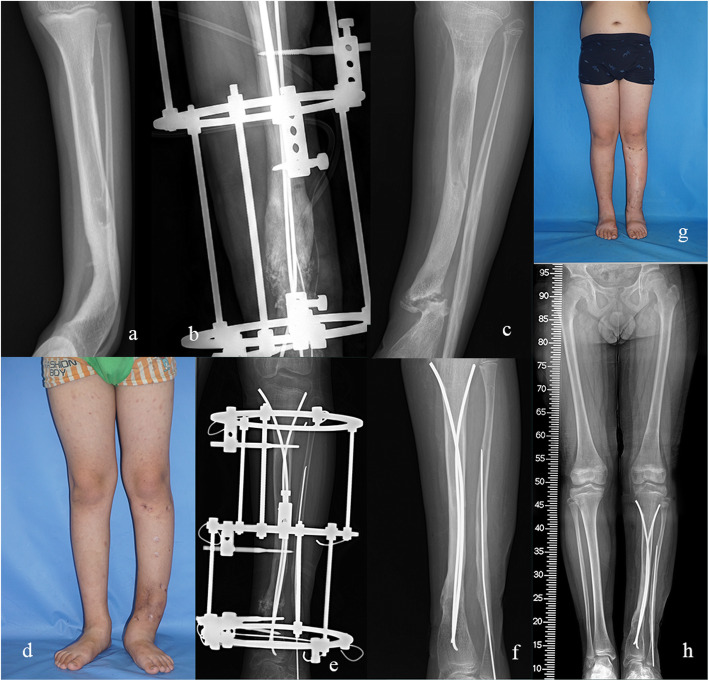

Fig. 4.

Anteroposterior radiograph of a 7.3-year-old boy with Crawford type II CPT (Case 3) (a). He underwent additional bone grafting and prolonged external fixation due to delayed union after initial combined surgery (b). However, refracture occurred 1 month after removal of Ilizarov fixator. He received cast immobilization and removal of broken nails at local medical center (c, d). In our institute, double TENs insertion and external fixation were applied (e). The fracture healed 5 months later and the external fixator was removed (f). Clinical and radiological appearance shows a well-aligned lower limb and sound union of the pseudarthrosis site (g, h)